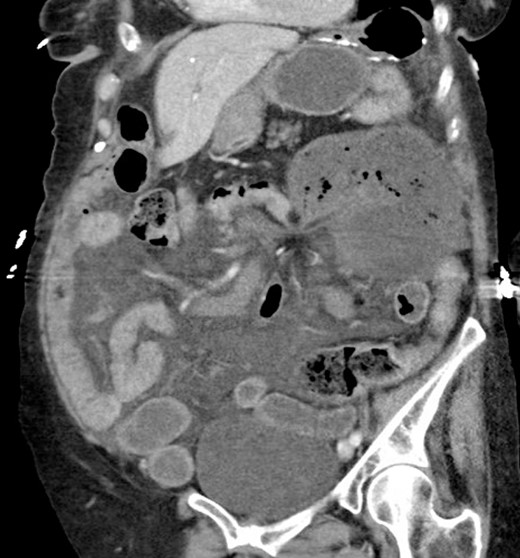

Computed tomography (CT) of her abdomen and pelvis with contrast revealed a dilated colon in the left upper quadrant with mesenteric edema and free fluid throughout the abdomen consistent with a cecal volvulus (Fig. 1).

Computed tomography showing cecal volvulus secondary to internal hernia.